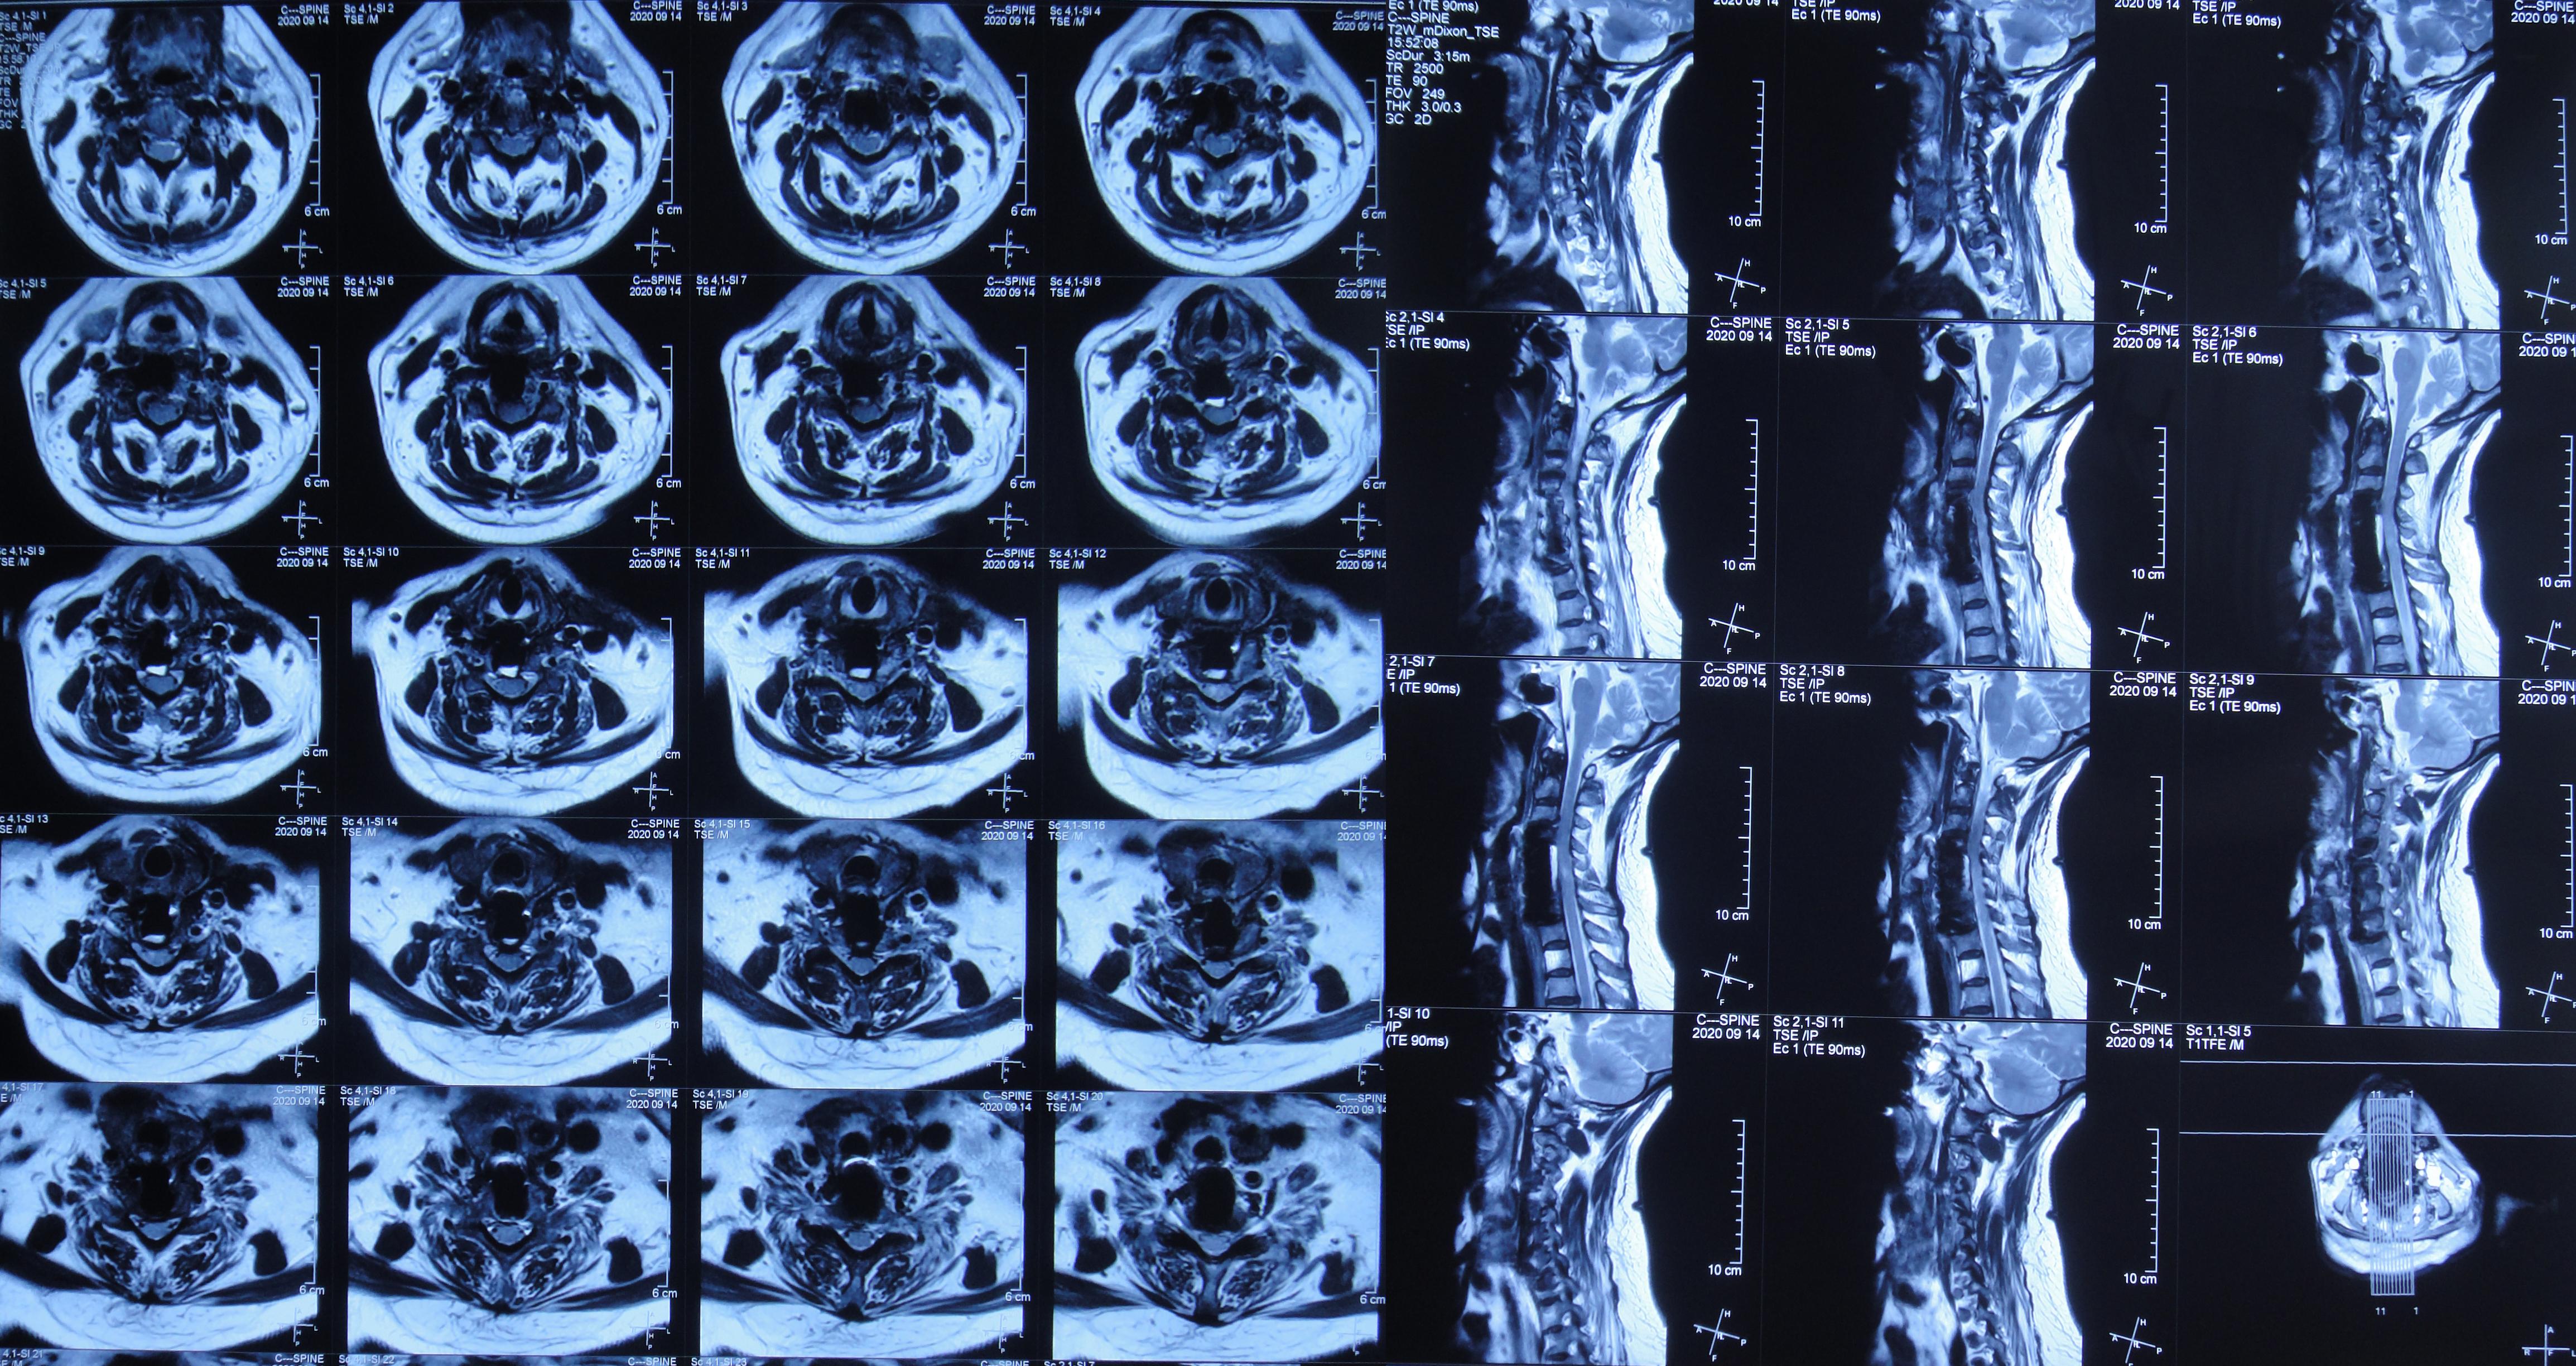

入院后第二天2020年4月12日查颈椎MR示颈椎病(脊髓型)( 图-2 )。

图-2: 2020年4月12日颈椎MR